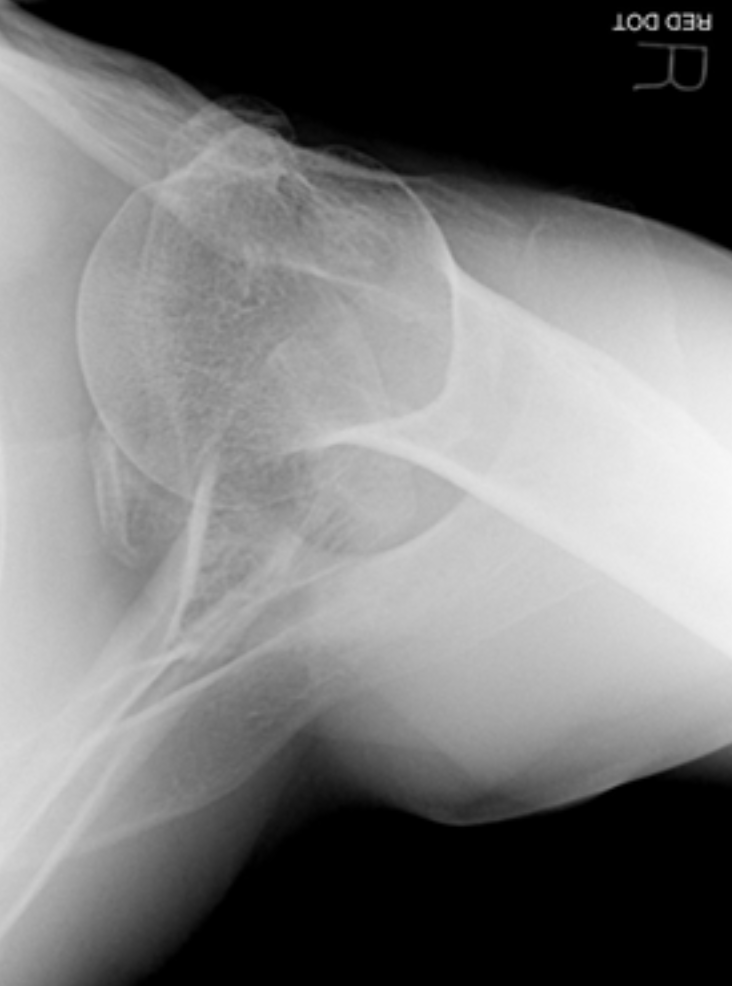

Normal Anatomy: Shoulder

A